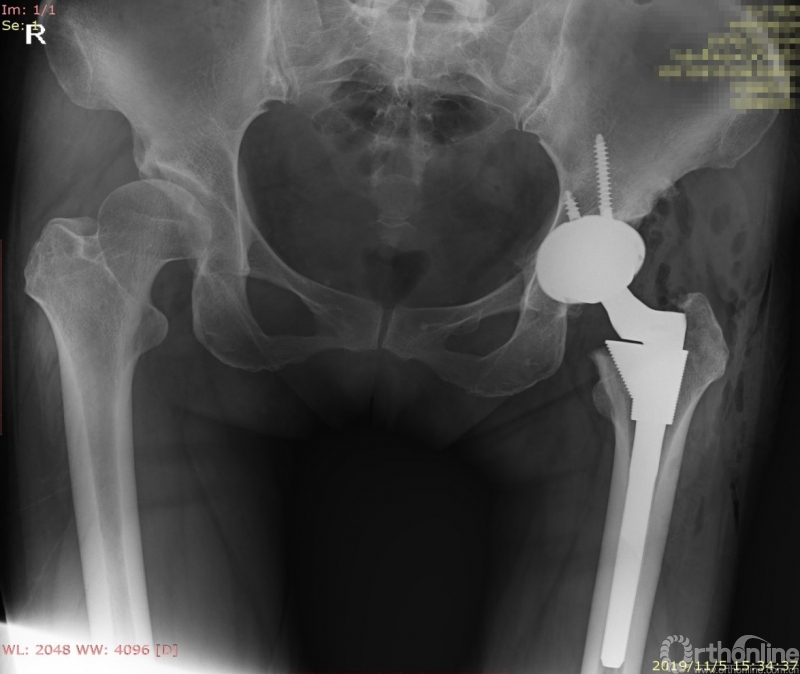

根据规划结果,术前模拟得到术后X线片,并精确显示出髋臼杯、股骨柄假体在原有CT图像上的轮廓位置,以供术者进行参考。由于术前准备充分,手术过程开展顺利,仅60分钟即完成了手术,术后X线与规划一致,患者功能恢复良好,术后第二天即可下地行走。

患者术后X线片